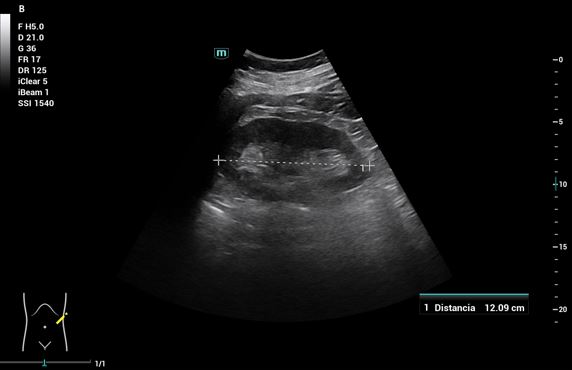

Pruebas complementarias: Sistemático de orina: microhematuria y ecografía abdominal: Riñones: (RD 11 cm, RI 12,09 cm), ecogenicidad, contornos y localización normales. RD: dilatación de la vía excretora Grado I dudosas imágenes de litiasis sin sombra acústica. No se evidencia líquido libre intrabdominal. Vejiga bien replecionada, jet ureteral bilateral simétrico, en trayecto del uréter derecho con Doppler color se observa artefacto de centelleo o efecto twinkling, que sugiere cálculo enclavado en unión vesicoureteral derecha.